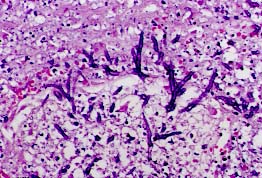

El tipo de respuesta tisular vendrá dada por el hallazgo de inflamación aguda, inflamación granulomatosa (Fig.7), necrosis (Fig.8), invasión vascular o trombosis. El potencial invasivo de un hongo sólo puede demostrarse a través del estudio del tejido (5).

08p.jpg (29290 bytes)

Fig.8

Para estudiar esta respuesta tisular, que puede ser de expresión variable, utilizaremos, además de la Hematoxilina-eosina ya citada, el Tricrómico de Masson o el Van-Giesson; para teñir fibras elásticas e identificar así los vasos trombosados podemos utilizar la tinción de Elastina o la de Van-Giesson-Elastina. Ante una necrosis caseosa debe realizarse la técnica de Ziehl-Nielsen, para descartar la presencia de bacilos ácido-alcohol resistentes.